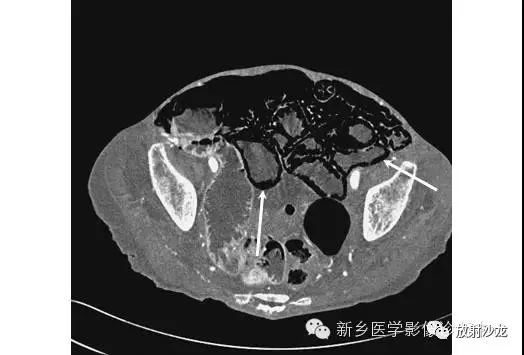

上图是一个孩子所做的腹部平片。有什么不好的发现(通过箭头的引导)?该平片显示坏死性小肠结肠炎患儿出现肠壁积气。肠壁积气是肠管缺血后的肠壁内的空气集聚。肠壁(箭头)出现线性的或曲线的透亮。在少数情况下,肠壁积气可以是慢性阻塞性肺病、腹部疾病、结缔组织疾病、使用类固醇类药物或化疗所致。

虽然X线平片足以诊断三分之二的肠壁积气病例,但CT可以更清楚地证明这种过程。CT上肠壁积气清晰可见(箭头)。